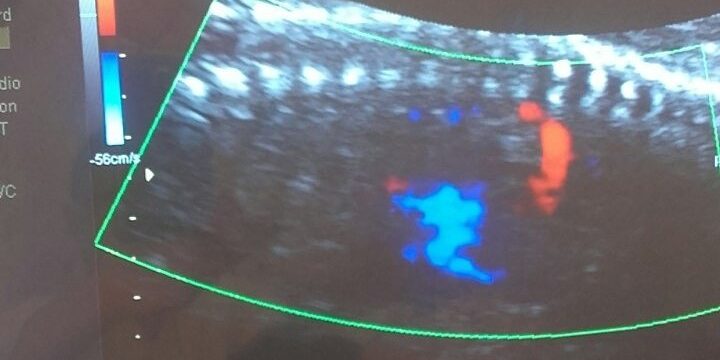

Феталната ехокардиографија претставува дијагностичка процедура којa овозможува да се види и процени структурата и функционирањето на кардиоваскуларниот систем на фетусот. Со оваа метода може уште во најраната бременост да се откријат вродените срцеви аномалии кај фетусот.

Трансвагиналната фетална ехокрадиографија се препорачува да се направи помеѓу 12 и 16 гестациска недела. Ова особено важи за високоризичните трудници. За разлика од трансвагиналната, трансабдоменалната најдобро е да се спроведе во периодот меѓу 19 и 24 гестациска недела. Имајќи ја предвид тежината и сложеноста на овој вид преглед, освен ултразвучниот апарат, потребна е и адекватна едукација на лекарите кои го вршат овој преглед.